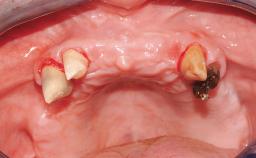

Immediate Loading of Eight Implants in the Maxilla and Six Implants in the Mandible and Final Restoration with Three-Unit and Four-Unit FDPs

Extensive scientific evidence has confirmed that immediately loaded implants with fixed full-arch provisional restorations can osseointegrate with success rates similar to conventionally or delayed loaded implants. A number of immediate-provisionalization techniques for edentulous jaws have been described. Some protocols differ when it comes to prefabricated provisional templates versus complete denture conversion; intrasurgical impressions versus direct relining; and cemented versus screw-retained provisional restorations. In this context, complete-denture conversion has been proposed for either intrasurgical impressions or direct relining. Another possibility is the utilization of a prefabricated provisional to be adapted either in the mouth (by direct relining) or in the laboratory (on a working model obtained from an intrasurgical impression).

Defining Characteristics Fully edentulous upper jaw to be rehabilitated with four or more implants

Modality 6+ implants with immediate loading

Defining Characteristics Fully edentulous upper jaw to be rehabilitated with an implant-borne fixed dental prosthesis

Loading Protocol Immediate